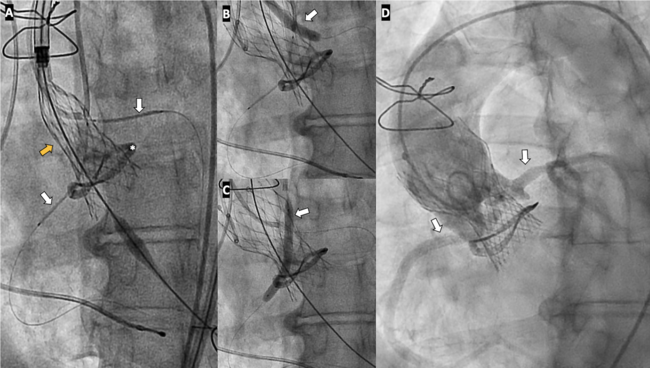

Video 1. Chimney stenting during transcatheter valve-in-valve aortic valve implantation. Two drug-eluting stents are positioned in the left main and right coronary arteries to protect the coronary arteries prior to valve deployment.

Video 2. Coronary angiography of the left coronary system demonstrating preserved flow in the left main coronary artery after surgery.

Video 3. Coronary angiography demonstrating extensive dissection of the right coronary artery ostium.